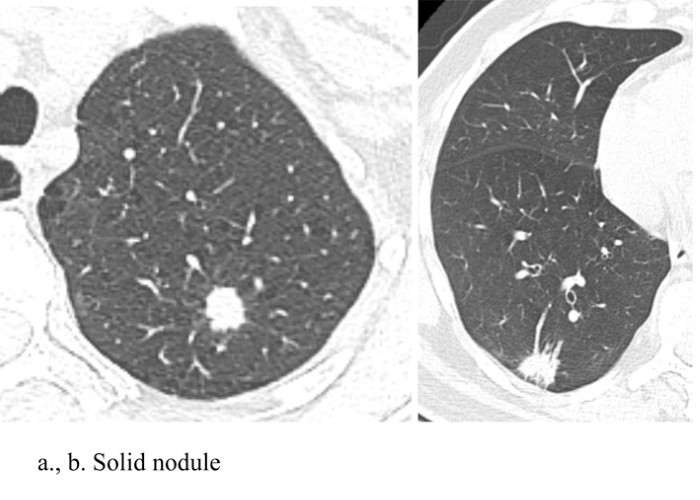

Chụp CLVT liều thấp cho phép xác định các nốt phổi bằng cách sử dụng liều bức xạ thấp nhất có thể. Điều này có thể thực hiện được thông qua việc sử dụng dòng điện và điện áp thấp hơn. Thử nghiệm tầm soát phổi Quốc gia (National Lung Screening Trial-NLST) đã thực hiện giảm liều bức xạ thông qua giảm dòng điện, với điện áp đỉnh là 120 kVp (140 kVp cho những BN béo), cường độ dòng điện từ 40 mA hoặc thấp hơn. Tùy thuộc vào máy chụp CLVT, liều hiệu quả trung bình là 1,4 milliSievert (mSv). Quá trình chụp CLVT được thực hiện trong thì hít vào mà không sử dụng chất cản quang tĩnh mạch. Hình ảnh chụp CLVT liều thấp trong chẩn đoán sớm UTP bao gồm: Nốt mờ đặc, nốt mờ bán đặc và hình ảnh nốt kính mờ (Hình 1), trong đó nốt mờ là hình ảnh hay gặp nhất [5, 6].

Hình 1: Nốt mờ đặc (a, b), bán đặc (c ,d) và nốt kính mờ (e, f).

Nguồn: Chiles C. (2014) [6].